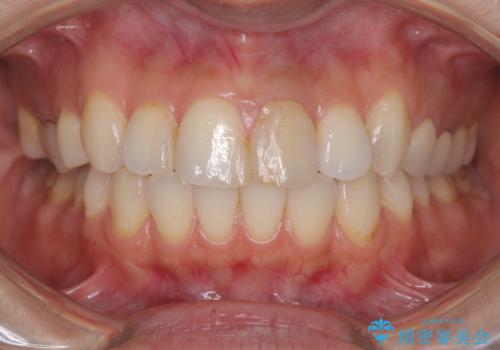

オールセラミッククラウンで治療を行い見た目の改善を行いました。

右上1もCRが入っており治療を勧めましたが、希望されず左上1のみ行いました。

色味は左上2に合わせたいとのご希望だったので、左上2に合わせています。